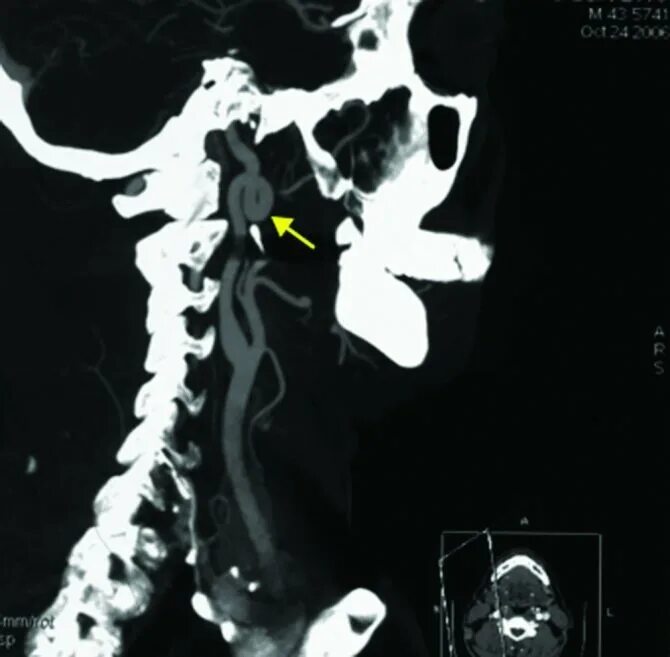

Кинкинг внутренней позвоночной артерии. койлинг артерии. койлинг внутренней сонной артерии. варианты отхождения позвоночных артерий.

Койлинг позвоночной артерии. s образная извитость позвоночной артерии. кинкинг и койлинг. s-образная извитость внутренней сонной артерии.

Кинкинг вса. патологическая извитость артерий (кинкинг). извитость сонных артерий кт. кинкинг позвоночной артерии мрт.

Койлинг внутренней сонной артерии. извитость внутренней сонной артерии. койлинг позвоночной артерии. кинкинг и койлинг.

Кинкинг и койлинг. синдром позвоночной артерии кт. кинкинг позвоночной артерии мрт. извитость сонных артерий кинкинг.

Кинкинг и койлинг. кинкинг позвоночной артерии. койлинг с 1. койлинг позвоночной артерии.

Кинкинг синдром внутренних сонных артерий. извитость позвоночной артерии v2. s образная извитость левой внутренней сонной артерии. s образная извитость позвоночной артерии.

Кинкинг вса. койлинг и кинкинг вса. кинкинг позвоночной артерии. патологическая извитость артерий (кинкинг).